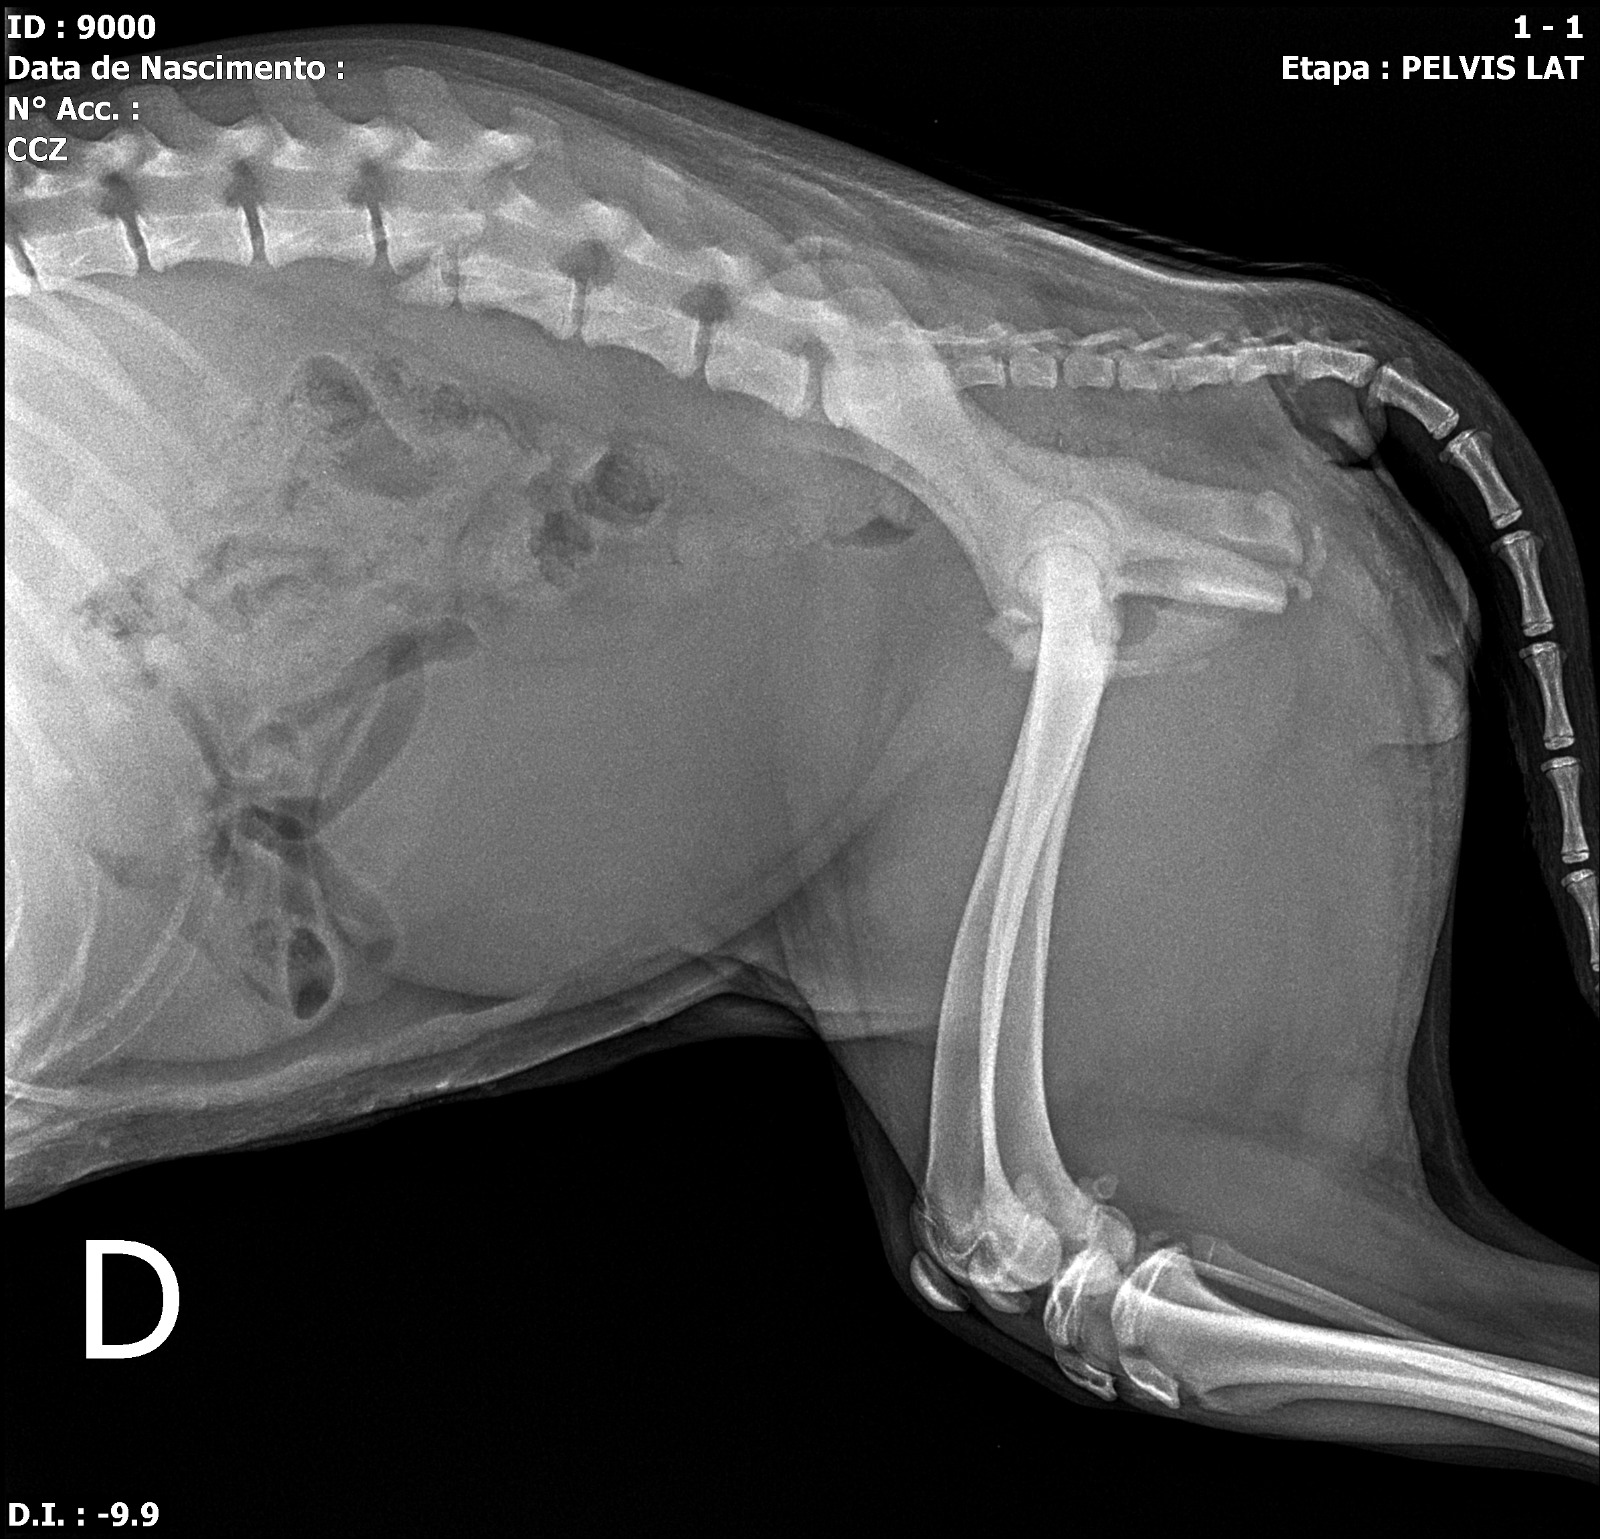

De acordo com atualização publicada no perfil do parlamentar, a cadela apresenta lesão medular associada a fratura toracolombar com instabilidade vertebral, quadro que resultou na perda dos movimentos das patas traseiras.